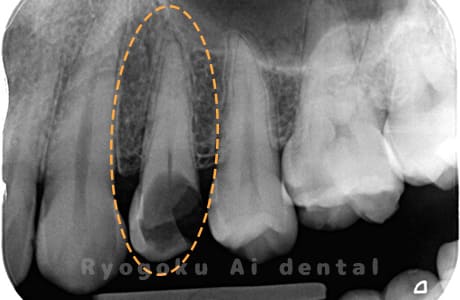

Case01

根管内の異物

- 原因

- 根管内異物(ファイル破折)による慢性根尖性歯周炎

- 治療期間

- 3ヶ月

- 治療内容

- マイクロスコープを使用した根管内異物除去並びにマイクロエンド

- 治療費用

- 121,000円(ファイル除去費用も込み)

他院で細い器具(ファイル)が根管内に破折した状態で、咬合痛を主訴に来院された患者様です。ファイルをマイクロスコープ下で除去し、根管治療を行ないました。

<リスク・副作用>

術後は痛み、腫れ、痺れなどの副作用が生じる場合があります。症状が再発する可能性があります。